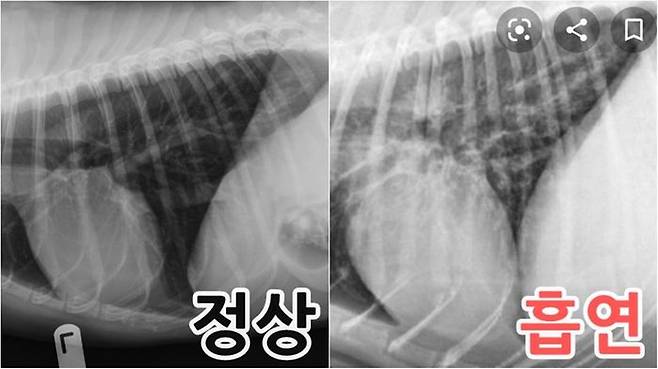

지난 3일 '미국수의사'라는 이름으로 활동하는 유튜버의 트위터 계정에는 "정상 vs 흡연가정 멍멍이의 흉부 엑스레이 비교"라는 설명과 함께 사진 2장이 올라왔습니다.

지난 3일 '미국수의사'라는 이름으로 활동하는 유튜버의 트위터 계정에는 "정상 vs 흡연가정 멍멍이의 흉부 엑스레이 비교"라는 설명과 함께 사진 2장이 올라왔습니다. 미국수의사는 코넬대 수의학과를 졸업하고 현재 미국에서 일하고 있는 수의사입니다.

사진을 보면 흡연 가정의 강아지 사진 속 장기가 더 부풀어있고 탁한 상태임을 확인할 수 있는데요, 작성자는 "동물들이 병원에 오면 보호자가 흡연자인지 아닌지 대번에 알 수 있다"고 지적하며 "간접흡연은 반려동물들의 폐암, 폐 질환, 만성 기관지염 등 각종 질병 확률을 높인다. 피려면 나가서 혼자 피세요"라고 일침을 가했습니다.